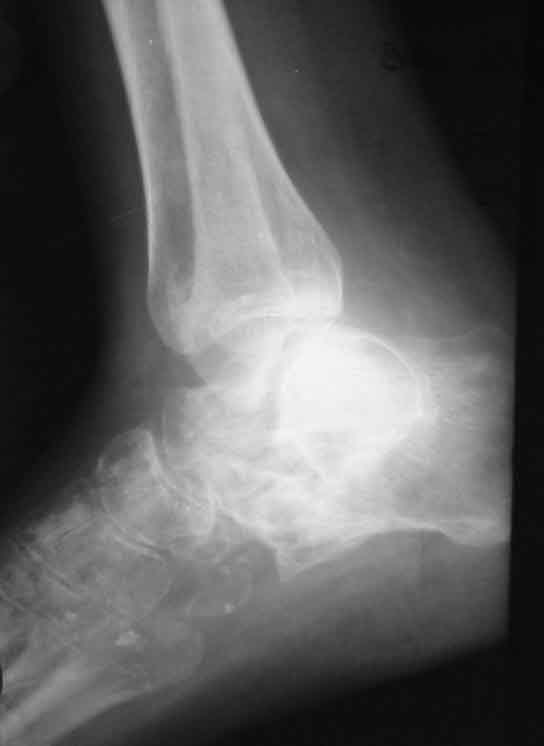

Застарелый вывих пяточной кости

Больная, 41 год, продавец, поступила в плановом порядке. Травма 1 год назад, вышла из двери второго этажа недостроенного дома с высоты 3 м. ДЗ. закр. перелом обеих лодыжек со смещением. Оскольчатый перелом пяточной кости. Вывих пяточной кости в подтаранном суставе кнаружи. При поступлении наложено вытяжение за пяточную кость 27.07 под в/в наркозом попытка устранения вывиха в подтаранном суставе (растягивался голеностопный сустав) безуспешна. Наложен гипс.

В последующем развился некроз кожного лоскута в области внутреней лодыжки 4х5 из-за натяжения кожи над внутренней лодыжкой. Консервативное лечение некроза кожи.Рана в области внутренней лодыжки зажила вторичным натяжением.В настоящее время Больная ходит на костылях с минимальной нагрузкой. При ходьбе беспокоят боли в стопе по подошве, в среднем отделе стопы, в области голеностопного сустава, переднего отдела стопы.Местно: имеется вальгусная деформация заднего отдела стопы, по внутренней поверхности стопы рубец - результат заживления раны вторичным натяжением, при пальпации резкая болезненность по подошвенно-внутренней поверхности стопы, движения в подтаранном суставе отсутствуют, при попытке их совершить появляется боль в проекции подтаранного сустава, сгибание разгибание в голеностопном суставе сохранены, болезненность появляется в крайних положениях сгибания-разгибания, имеются пронационные супинационные движения в голеностопном суставе.ДЗ Сросшийся со смещением перелом обеих лодыжек, подвывих книзу, сросшийся со смещением перелом пяточной кости вывих пяточной кости кнаружи.Коллеги, поделитесь мнением, что делать в такой ситуации?Снимок 1

Снимок 3

Снимок 4